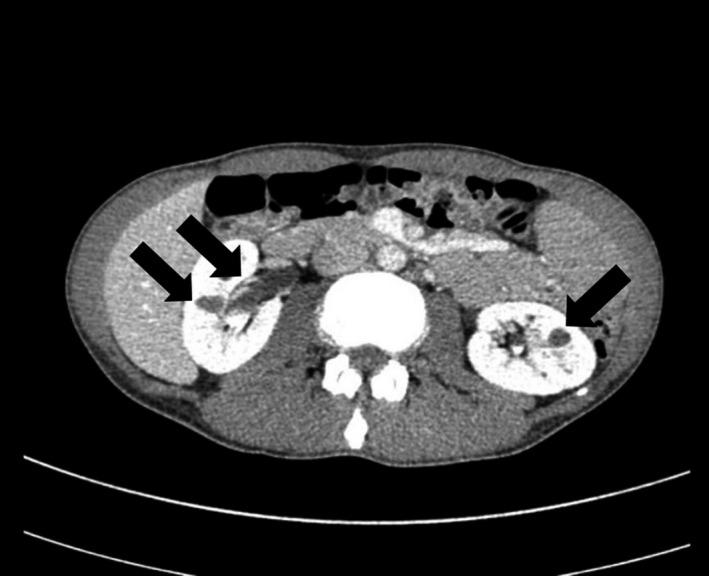

A 34-year-old man visited our Department of Gastroenterology and Metabolism, Nagoya City University Graduate School of Medical Sciences, Nagoya, Japan, because of dry mouth and weight loss. His plasma glucose level was 32.8 mmol/L and serum levels of ketone bodies were increased, but with metabolic alkalemia. He was also suffering from renal tubular hypomagnesemia and hypokalemia. Abdominal computed tomography showed bilateral renal cysts. These findings were suggestive of maturity-onset diabetes of the young type 5. Genetic testing showed heterozygous hepatocyte nuclear factor 1 beta gene deletion. In the present case, it seemed reasonable to view hepatocyte nuclear factor 1 beta gene deletion as the common cause of maturity-onset diabetes of the young type 5-associated diabetic ketoacidosis and tubular malfunction-induced hypokalemic alkalosis. This case exemplifies the importance of hepatocyte nuclear factor 1 beta gene abnormality as a potential cause of diabetic ketoacidosis with alkalemia.

一位 34 岁男性因口干和体重减轻到日本名古屋市立大学研究生院医学部消化和代谢科就诊。他的血浆葡萄糖水平为 32.8mmol/L,血清酮体水平升高,但伴有代谢性碱中毒。他还患有肾小管低镁血症和低钾血症。腹部计算机断层扫描显示双侧肾囊肿。这些发现提示青年发病的成年型糖尿病 5 型。基因检测显示杂合性肝细胞核因子 1β 基因突变。在本病例中,将肝细胞核因子 1β 基因突变视为青年发病的成年型糖尿病 5 型相关糖尿病酮症酸中毒和管状功能障碍引起的低钾性碱中毒的共同原因似乎是合理的。该病例说明了肝细胞核因子 1β 基因异常作为伴碱中毒的糖尿病酮症酸中毒的潜在病因的重要性。